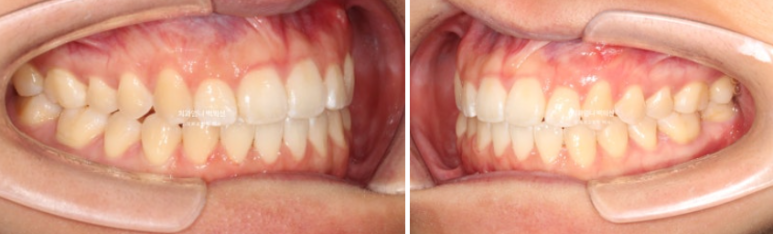

24.12~25.06

개방교합 뿐 아니라 철사의 변형으로 쓰러져 있던 송곳니도 세웠습니다.

원래 좋았던 교합은 잘 유지가 되었습니다.

6개월간 앞니 부분교정의 변화 치고 드라마틱 합니다.